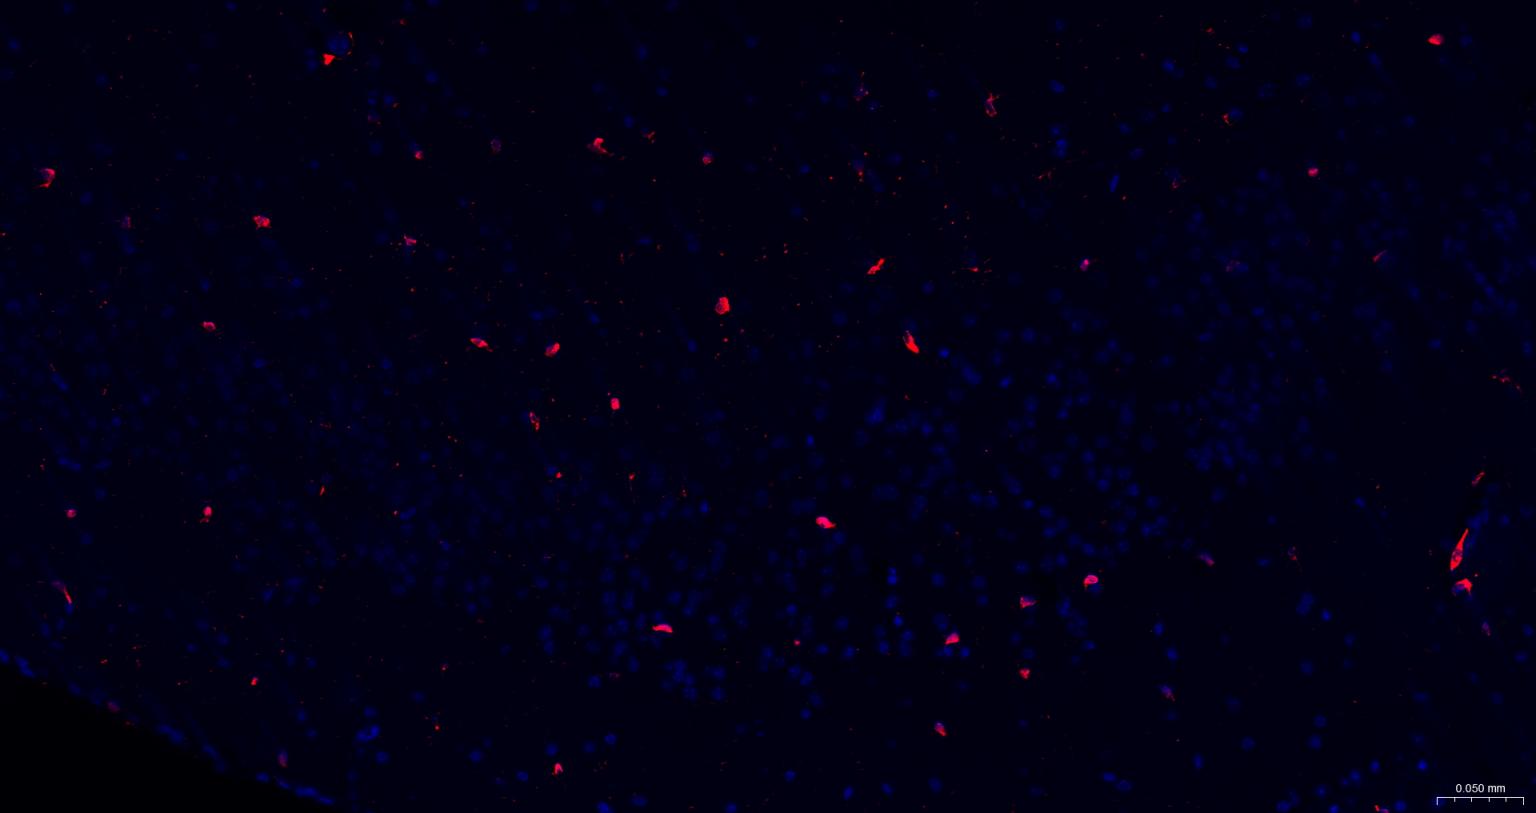

Paraformaldehyde-fixed, paraffin embedded Human Left Parietal Lobe; Antigen retrieval by boiling in sodium citrate buffer (pH6.0) for 15 min; The section was incubated with AIF1 / Iba1 Polyclonal Antibody, Unconjugated (bs-1363R) at 1:200 overnight at 4°C. Followed by conjugated Goat Anti-Rabbit IgG antibody (Red, bs-0295G-BF594), DAPI (blue, C02-04002) was used to stain the cell nuclei.

Paraformaldehyde-fixed, paraffin embedded Rat Cerebrum; Antigen retrieval by boiling in sodium citrate buffer (pH6.0) for 15 min; The section was incubated with AIF1 / Iba1 Polyclonal Antibody, Unconjugated (bs-1363R) at 1:200 overnight at 4°C. Followed by conjugated Goat Anti-Rabbit IgG antibody (Red, bs-0295G-BF594), DAPI (blue, C02-04002) was used to stain the cell nuclei.

Paraformaldehyde-fixed, paraffin embedded Mouse Cerebrum; Antigen retrieval by boiling in sodium citrate buffer (pH6.0) for 15 min; The section was incubated with AIF1 / Iba1 Polyclonal Antibody, Unconjugated (bs-1363R) at 1:200 overnight at 4°C. Followed by conjugated Goat Anti-Rabbit IgG antibody (Red, bs-0295G-BF594), DAPI (blue, C02-04002) was used to stain the cell nuclei.